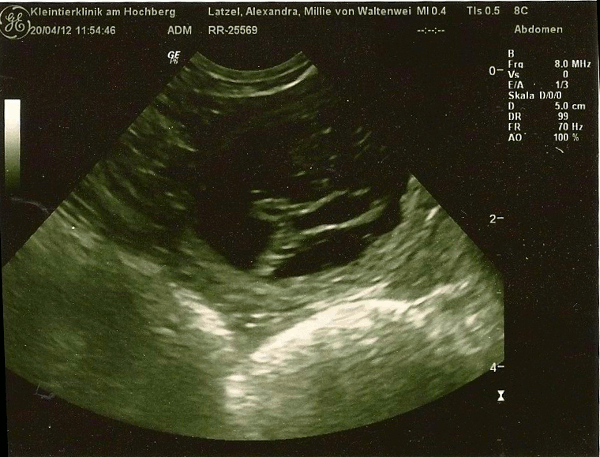

| Hurra, jetzt ist es amtlich, Millie ist schwanger! |

|